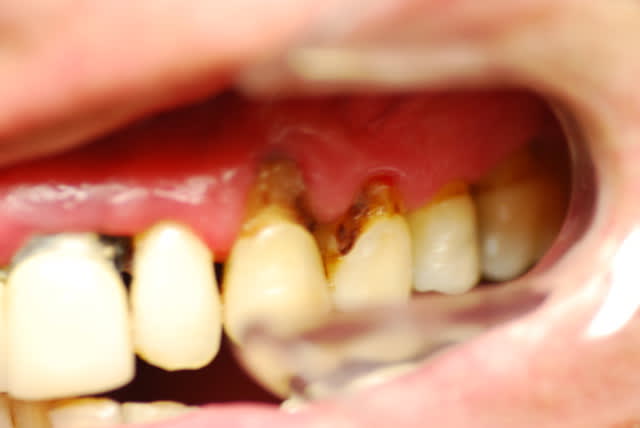

Je viens de revoir le patient et je peux vous apporter quelques précisions ainsi que des photos( désolé si la qualité n'est pas parfaite).

Patient de 45 ans, fumeur, motivé mais ne pouvant se payer d'implants.

Il a déjà vu plusieurs confrères qui lui ont proposé uniquement ( selon ses dires) une solution implantaire pour 12-11-21-22-23. Il souhaite du fixe...

En ce qui concerne la paro, la 12 est en mobilité stade 2, la 22 en stade 1 les autres étant non mobiles. Le sondage de 12 à 22 est de 3 mm, sauf en mésiale de 12 ( 6mm). La gencive est inflammatoire ( logique à la vue de l'inadaptation des couronnes, et des caries radiculaires).

Je pense lui proposer la solution du bridge avec 13,11,21,22, 24,25., même si la 13 est saine... Je prévoyais de reprendre l'endo de 22 mais la taille du tenon et sa longueur m'ont refroidi, peut être qu'une chir endo et obturation à rétro serait plus appropriées... Je prévois bien sur un surfaçage ainsi qu'un assainissement paro, une fois le bridge provisoire en place.

Tu as surtout un gros chantier paro à gérer. Et je ne pense pas que le tenon de la 22 soit si difficile à descendre, accessoirement l'endo de la 11 est aussi à revoir ( et là le tenon semble plus maousse ).

La 23 est hyper moche, la 12 encore plus...